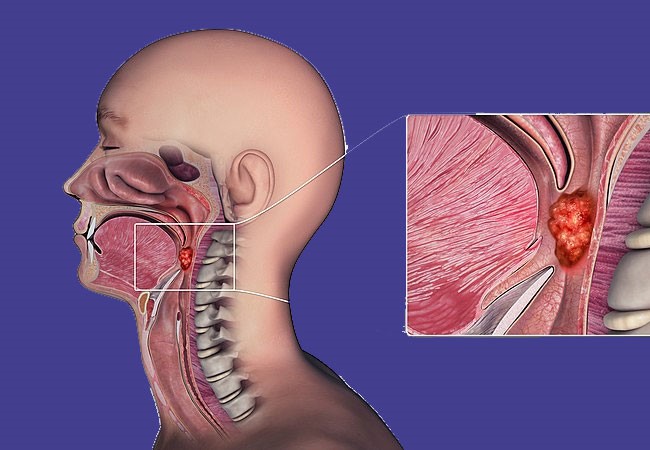

یک نکته حائز اهمیت در مورد سرطان حلق این است که این نوع سرطان ممکن است در بخشهای مختلفی از گلو ایجاد شود، که به همین دلیل انواع گوناگونی دارد. حلق با طول حدود شش اینچ، از پشت گلو تا ابتدای مری امتداد دارد. این ساختار اصلی شامل:

- نازوفارنکس (بخش پشتی حفره بینی)

- اوروفارنکس در پشت حفره دهان (کام نرم)

- حنجره (که به مری منتهی میشود)

این بخشها با غشاهای مخاطی، بافت هم بند، غدد، بافت لنفاوی، و ماهیچههای پشت حلق تشکیل شدهاند. همگی این اجزا ممکن است به سرطان مبتلا شوند.

سرطان نازوفارنکس نوعی سرطان است که در بخشی از گلو به نام نازوفارنکس آغاز میشود. این بخش از گلو درست پشت بینی واقع شده و شامل مرتبه بینی، تخمیر (آمیگداله) و قسمت پشتی گلو میشود. سرطان نازوفارنکس ممکن است از سلولهای مختلف در این منطقه نشأت گرفته و معمولاً به عنوان یکی از زیر گروههای سرطان حلق در نظر گرفته شود. علائم آن میتوانند شامل درد، خونریزی، یا تغییرات در صدا باشند. برای تشخیص و درمان سرطان نازوفارنکس، مشاوره با متخصص گوش و حلق و بینی یا متخصص آنکولوژی مورد نیاز است.

سرطان اوروفارنکس یک نوع سرطان است که در بخشی از گلو به نام اوروفارنکس آغاز میشود. این بخش از گلو درست در پشت دهان و شامل لوزهها نیز میشود. این نوع سرطان ممکن است از سلولهای مختلف در این منطقه نشأت گرفته و معمولاً به عنوان یکی از زیر گروههای سرطان حلق در نظر گرفته شود.

سرطان حنجره نوعی از سرطان است که در قسمت پایین گلو آغاز میشود و به سرعت به طول حنجره گسترش مییابد. این بخش از گلو در محدودهای که به مری منتهی میشود و به طور مشخص در ناحیه پایینی گلو قرار دارد، درگیر میشود.سرطان هیپوفارنکس یا حنجره ممکن است علائمی همچون تغییرات در صدا، درد یا سختی در بلعیدن ایجاد کند. برای تشخیص و درمان سرطان حنجره، مراجعه به متخصص گوش و حلق و بینی یا متخصص آنکولوژی ضروری است.